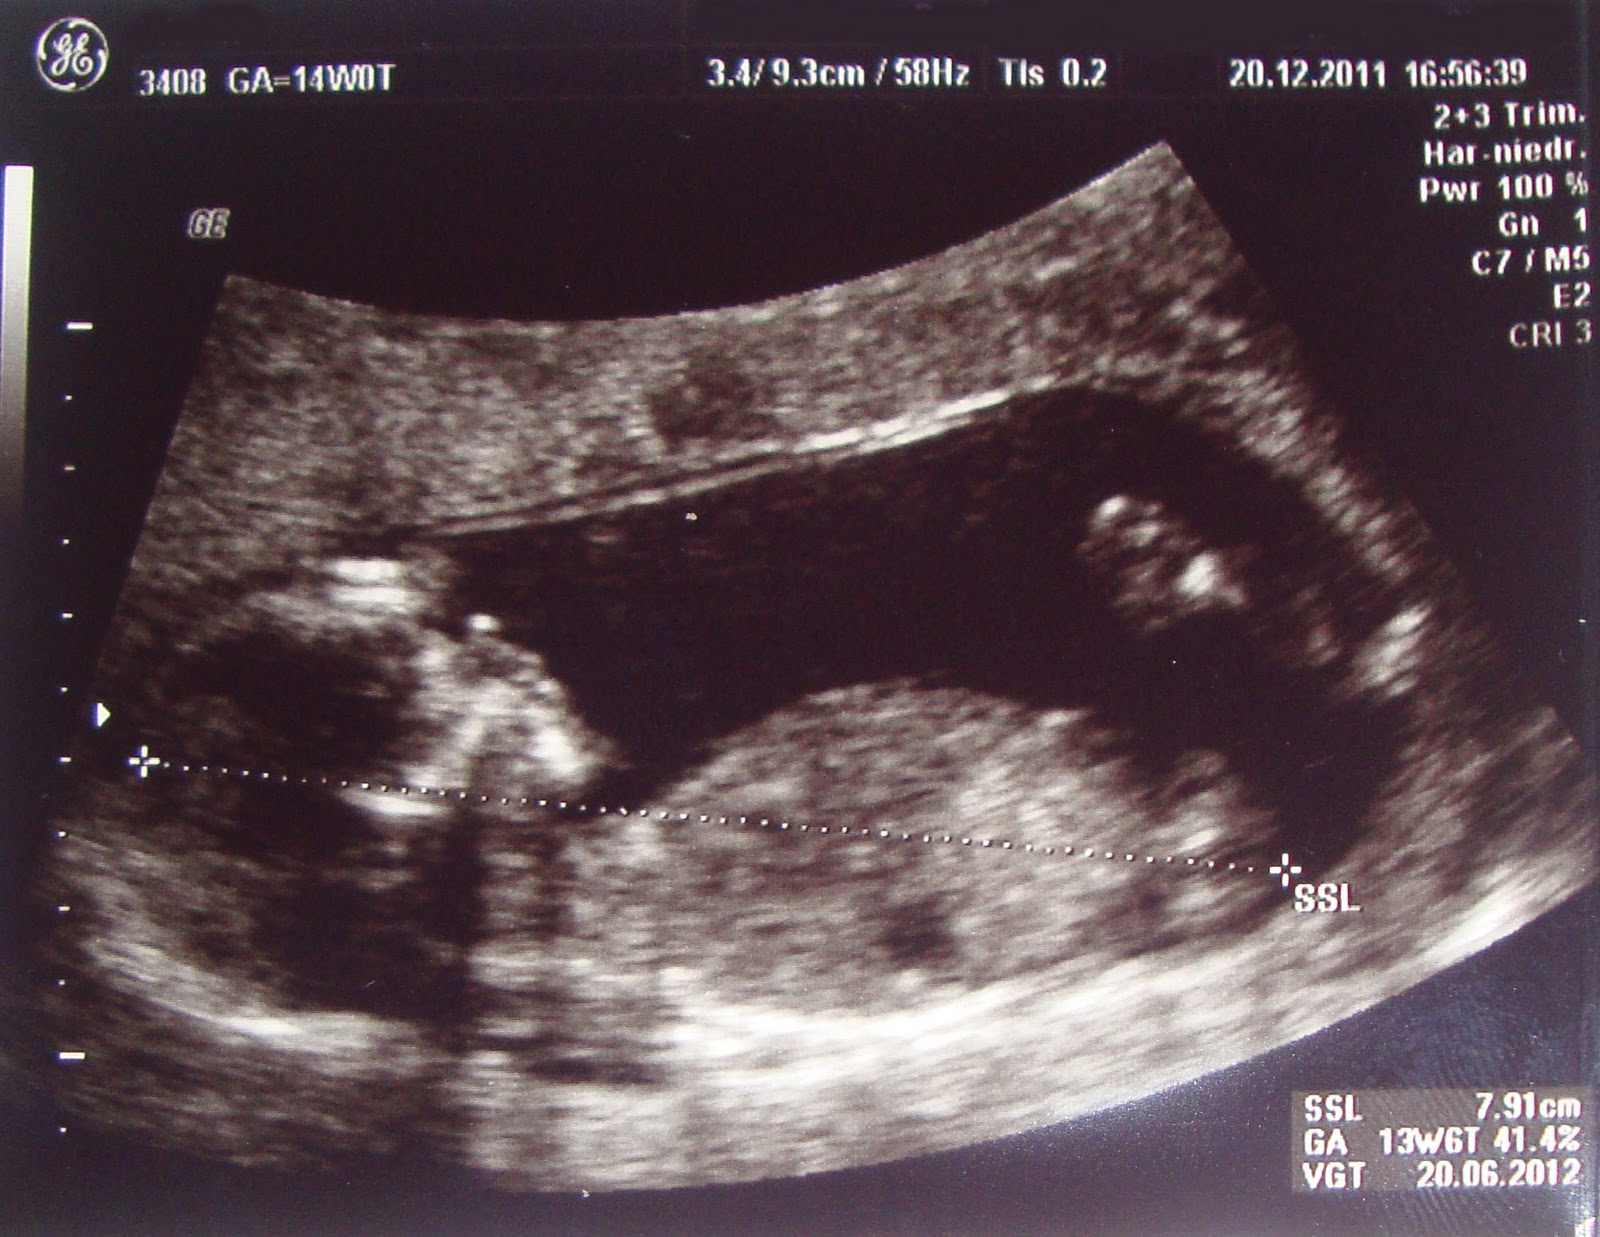

Und da mir seitdem 24 Stunden am Tag übel war und ich genauso lange schlafen könnte, habe ich mir erstmal eine kleine Blog-Pause verordnet. Jetzt bin ich in der 14. SSW und nun geht es mir wieder besser. Gestern hatte ich meine 3. VU beim FA. Alles super!

Der Arzt fragte mich dann, ob ich denn das Geschlecht wissen möchte. Da ich ein sehr neugieriger Mensch bin, wollte ich das natürlich sehr gerne wissen.

Und … es wird ein ? Man konnte nichts erkennen. Einerseits zwar schade, aber andererseits kann ich mir nun noch einen weiteren Monat ausmalen, was es werden könnte. Auch schön 😉